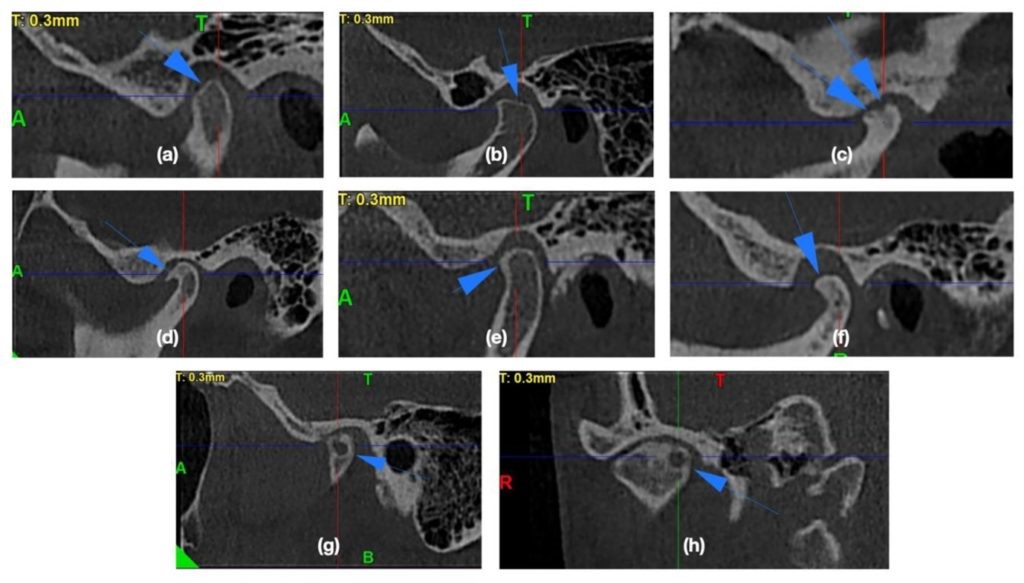

3. CBCT trong chẩn đoán răng khôn mọc lệch, mọc ngầm:

Răng khôn hàm dưới hai bên của mỗi người có đặc điểm là ít khi mọc thẳng như các răng khác trên cung hàm, có tỷ lệ cao mọc lệch hay ngầm, ảnh hưởng âm thầm đến răng phía trước nó là răng cối lớn thứ hai từ đó gây viêm lợi trùm, sâu thân răng, chết tuỷ mà bệnh nhân ít khi có triệu chứng nhận biết.

Răng khôn hàm dưới là răng trên cung hàm nằm gần với ống thần kinh răng dưới nhất và có nguy cơ cao chèn ép hay kẹp ống thần kinh, gây nguy cơ chấn thương thần kinh cao khi phẫu thuật nhổ răng khôn. Nhờ có sự giúp đỡ của CBCT, bác sĩ có thể lường trước được mối liên quan của dây thần kinh với chân răng khôn cũng như quyết định thực hiện kỹ thuật nhổ răng khôn trong một lần duy nhất hay chỉ cắt thân răng khôn, chờ chân răng trồi lên.

Răng khôn hàm dưới mọc lệch chèn ép thần kinh trên phim CBCT